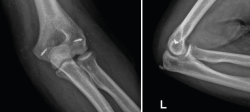

3. Radiografías simples de codo en proyección anteroposterior (AP) y lateral (Figura 5).

Figura 5. Radiografías simples de codo en proyección anteroposterior y lateral. En estas radiografías puede apreciarse una luxación posterolateral de un codo izquierdo, además de fractura de la cabeza del radio y fractura de la punta de la coronoides.